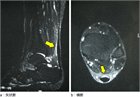

1. アキレス腱症とアキレス腱付着部症の病態をしっかり区別する必要がある(推奨度1)

1. 診断、治療、経過評価に、超音波画像検査が有用である(推奨度2